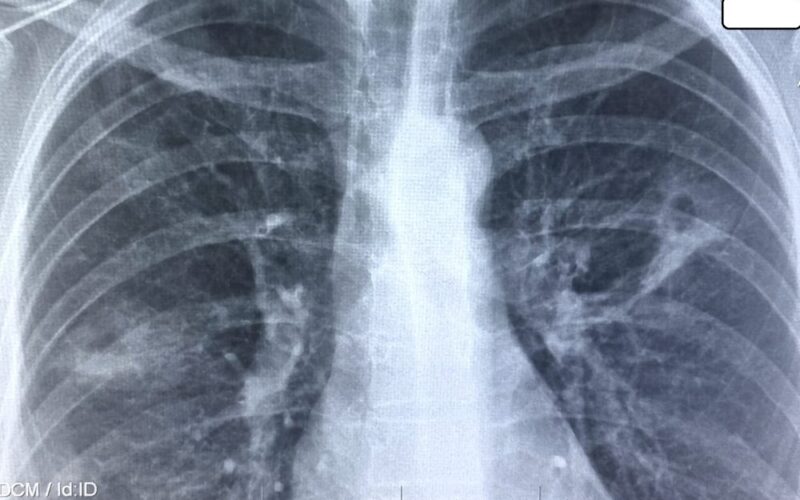

Pe fondul reducerilor semnificative ale finanțării pentru programele de sănătate publică locale, naționale și internaționale, tuberculoza (TB) – inclusiv formele rezistente la medicamente – riscă să revină în forță atât în SUA, cât și la nivel global, scrie The Guardian.